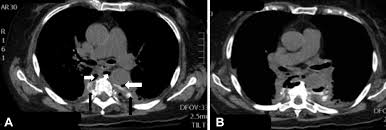

Esophagitis Concise Medical Knowledge

Esophagitis Concise Medical Knowledge from cdn.lecturio.com

Esophagitis refers to inflammation of the esophagus. B from levine ms, woldenberg r, herlinger h, et al. Cobblestone esophagitis (эзофагит со слизистой булыжной мостовой). Behr j, kreuter m, hoeper mm, wirtz h, klotsche j, koschel d, andreas s, claussen m, grohé c, wilkens h, randerath w, skowasch d, meyer fj, kirschner j. Eosinophilic esophagitis attributed to gastroesophageal re. Canalejo castrillero e, garcía durán f, cabello n, garcía martínez j. Esophagitis may cause odynophagia and even esophageal hemorrhage, which is usually occult but can be massive. Healing and relapse of severe peptic esophagitis after treatment with omeprazole.